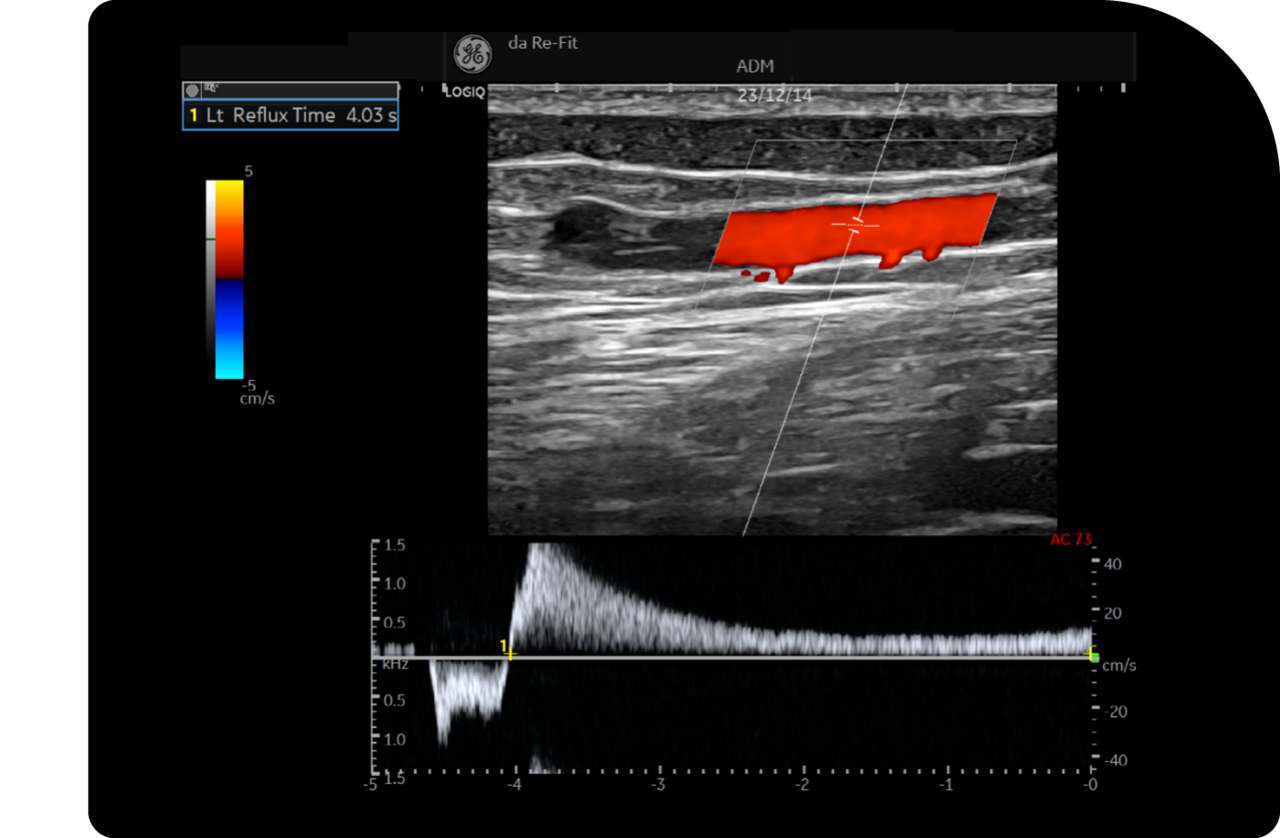

도플러 초음파 정밀 검사

초음파 정밀 검사를 통해 다리의 상태를 실시간으로 확인하여

혈관의 확장 정도, 혈액의 역류 상태 등을 정확하게 진단합니다.

검사 결과를 바탕으로 하지정맥류의 심각도를 판단하고

이를 통해 최적의 수술 또는 치료 방법을 결정합니다.